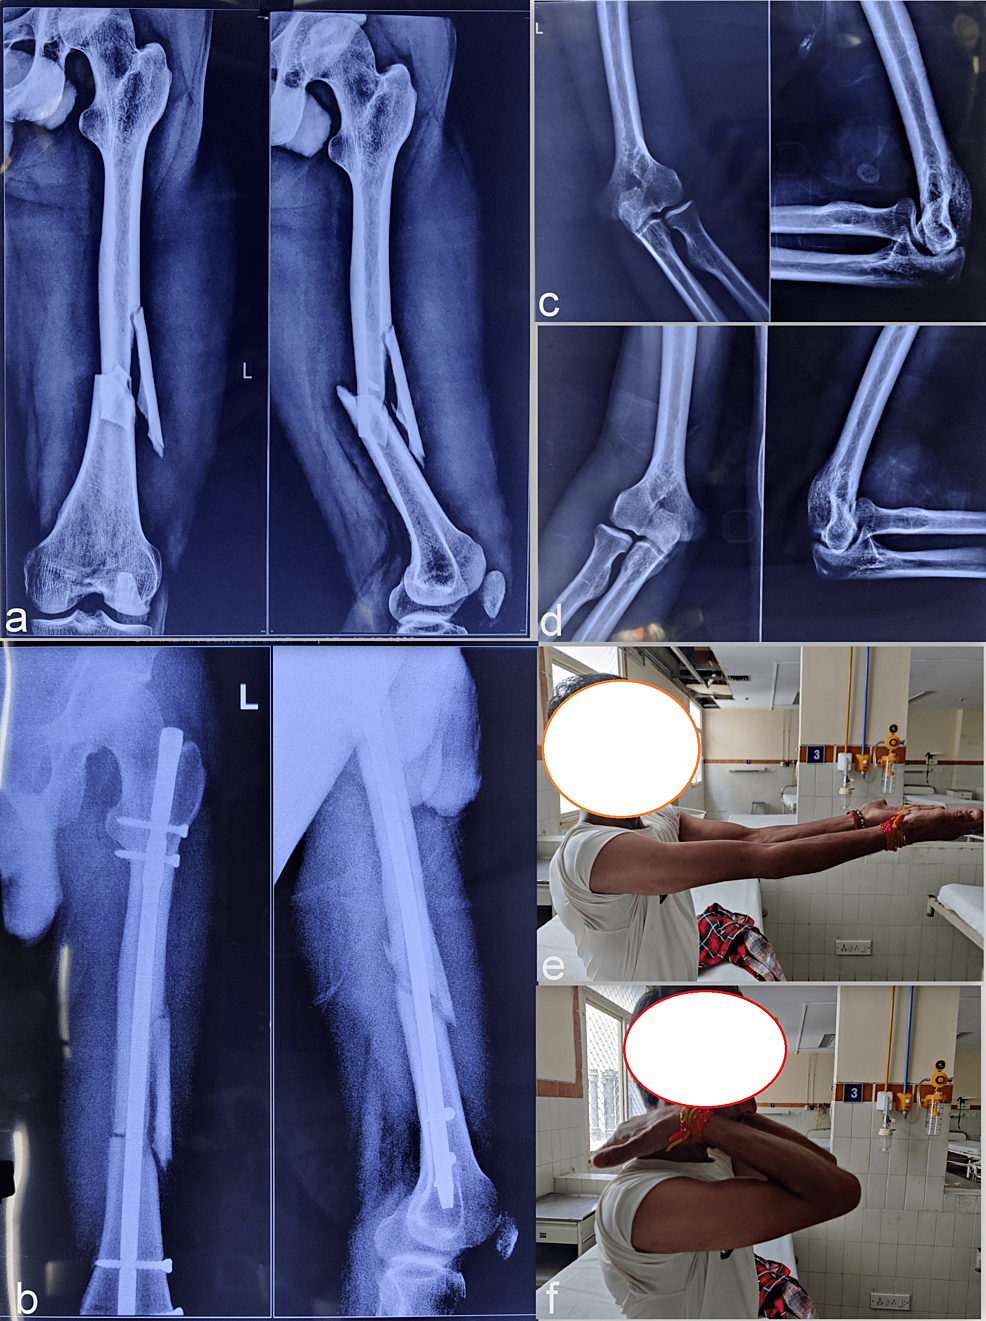

From www.cureus.com

Cureus NailPatella Syndrome A Case Series From Northern India Floating Patella Syndrome patellar instability is a condition characterized by patellar subluxation or dislocation episodes as a result of injury, ligamentous laxity. floating knee is used to describe fractures of the ipsilateral femur and tibia. patellar subluxation, or a dislocation of the knee cap, requires a diagnosis and treatment from a doctor. You may need a brace, crutches,. a. Floating Patella Syndrome.